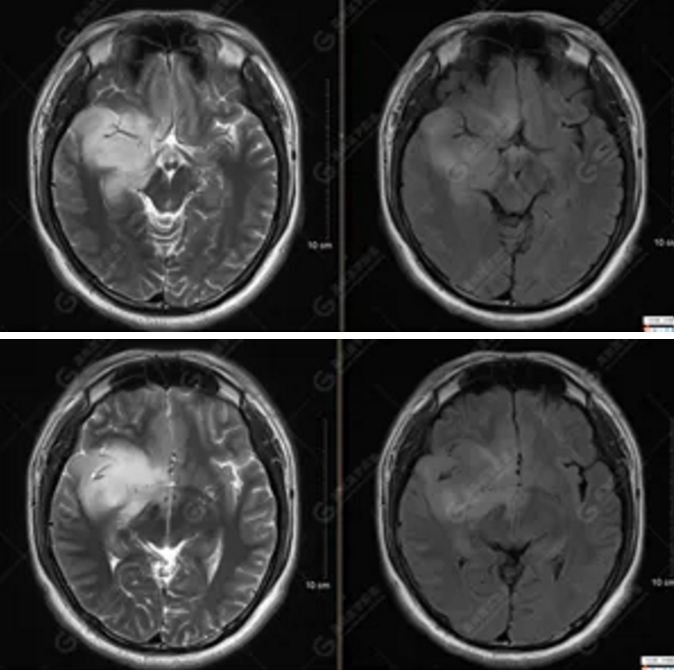

【MRI平掃及增強(qiáng)檢查所見(jiàn)】右側(cè)額顳島葉、右側(cè)海馬及右側(cè)基底節(jié)區(qū)見(jiàn)一團(tuán)塊狀異常信號(hào)影,累及右側(cè)下丘腦及視交叉,大小約5.1cm×4.5cm×4.3cm,呈長(zhǎng)T1長(zhǎng)T2信號(hào),F(xiàn)LAIR序列呈等、稍高信號(hào),DWI序列呈稍高信號(hào),ADC圖高信號(hào),增強(qiáng)后無(wú)明顯強(qiáng)化;病灶周?chē)?jiàn)片狀長(zhǎng)T1長(zhǎng)T2水腫信號(hào)影,F(xiàn)LAIR序列呈高信號(hào),病灶內(nèi)見(jiàn)右側(cè)大腦中動(dòng)脈穿行。余腦實(shí)質(zhì)內(nèi)未見(jiàn)局灶性信號(hào)異常,增強(qiáng)后未見(jiàn)異常強(qiáng)化。右側(cè)側(cè)腦室輕度受壓,余腦室、腦池大小、形態(tài)均正常,中線(xiàn)結(jié)構(gòu)居中

圖1為多體素MRS檢查,感興趣區(qū)為正常腦組織的MRS表現(xiàn)。圖2為單體素MRS,右側(cè)顳葉病灶內(nèi)NAA峰明顯下降,Cho峰明顯升高,NAA/Cr值為0.1,Cho/Cr值為3.64。